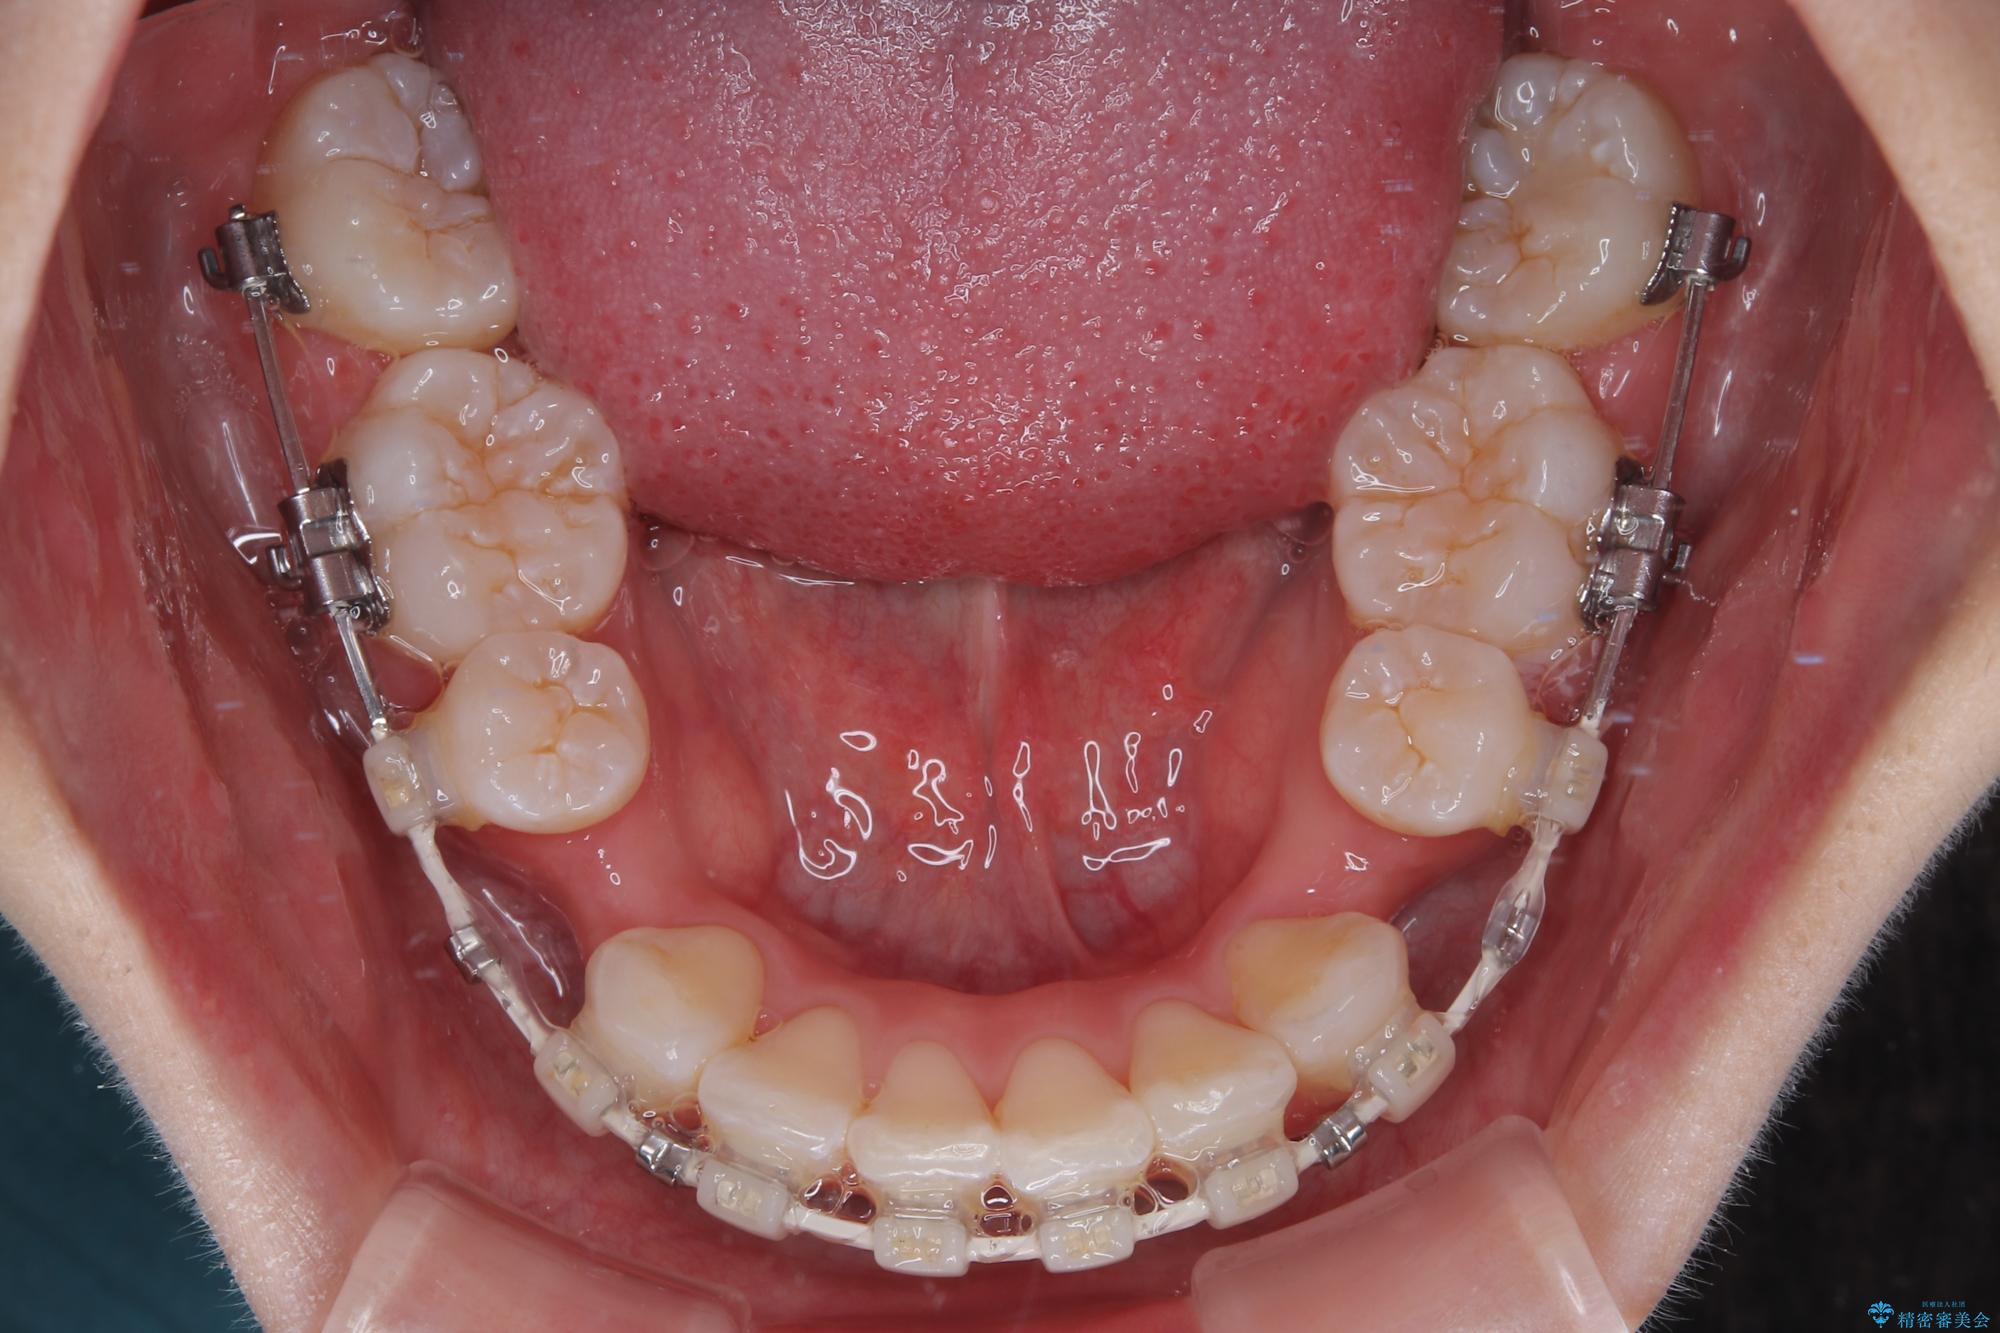

- 矯正装置

- 審美装置

- 2年

- 10-30回

下顎はデコボコが気になっていたため、上下左右第一小臼歯4本を抜去して、ワイヤー装置にて口元の突出感を改善するよう矯正治療を行うこととしました。